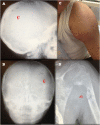

Mutations in the genes coding for cytokines, receptors, second messengers, and transcription factors of interferon gamma (IFN-γ) immunity cause Mendelian susceptibility to mycobacterial disease (MSMD). We report the case of a 7-year-old male patient with partial dominant (PD) IFN-γ receptor 1 deficiency who had suffered from multifocal osteomyelitis attributable to bacille Calmette-Guérin vaccination since the age of 18 months. He developed hemophagocytic lymphohistiocytosis (HLH), a hyper-inflammatory complication, and died with multiorgan dysfunction, despite having been diagnosed and treated relatively early. Patients with PD IFN-γR1 deficiency usually have good prognosis and might respond to human recombinant subcutaneous IFN-γ. Several monogenic congenital defects have been linked to HLH, a catastrophic "cytokine storm" that is usually ascribed to lymphocyte dysfunction and thought to be triggered by interferon gamma. This is the sixth patient with both MSMD and HLH of whom we are aware. The fact that patients with macrophages that cannot respond to IFN-γ still develop HLH, bring these assumptions into question.